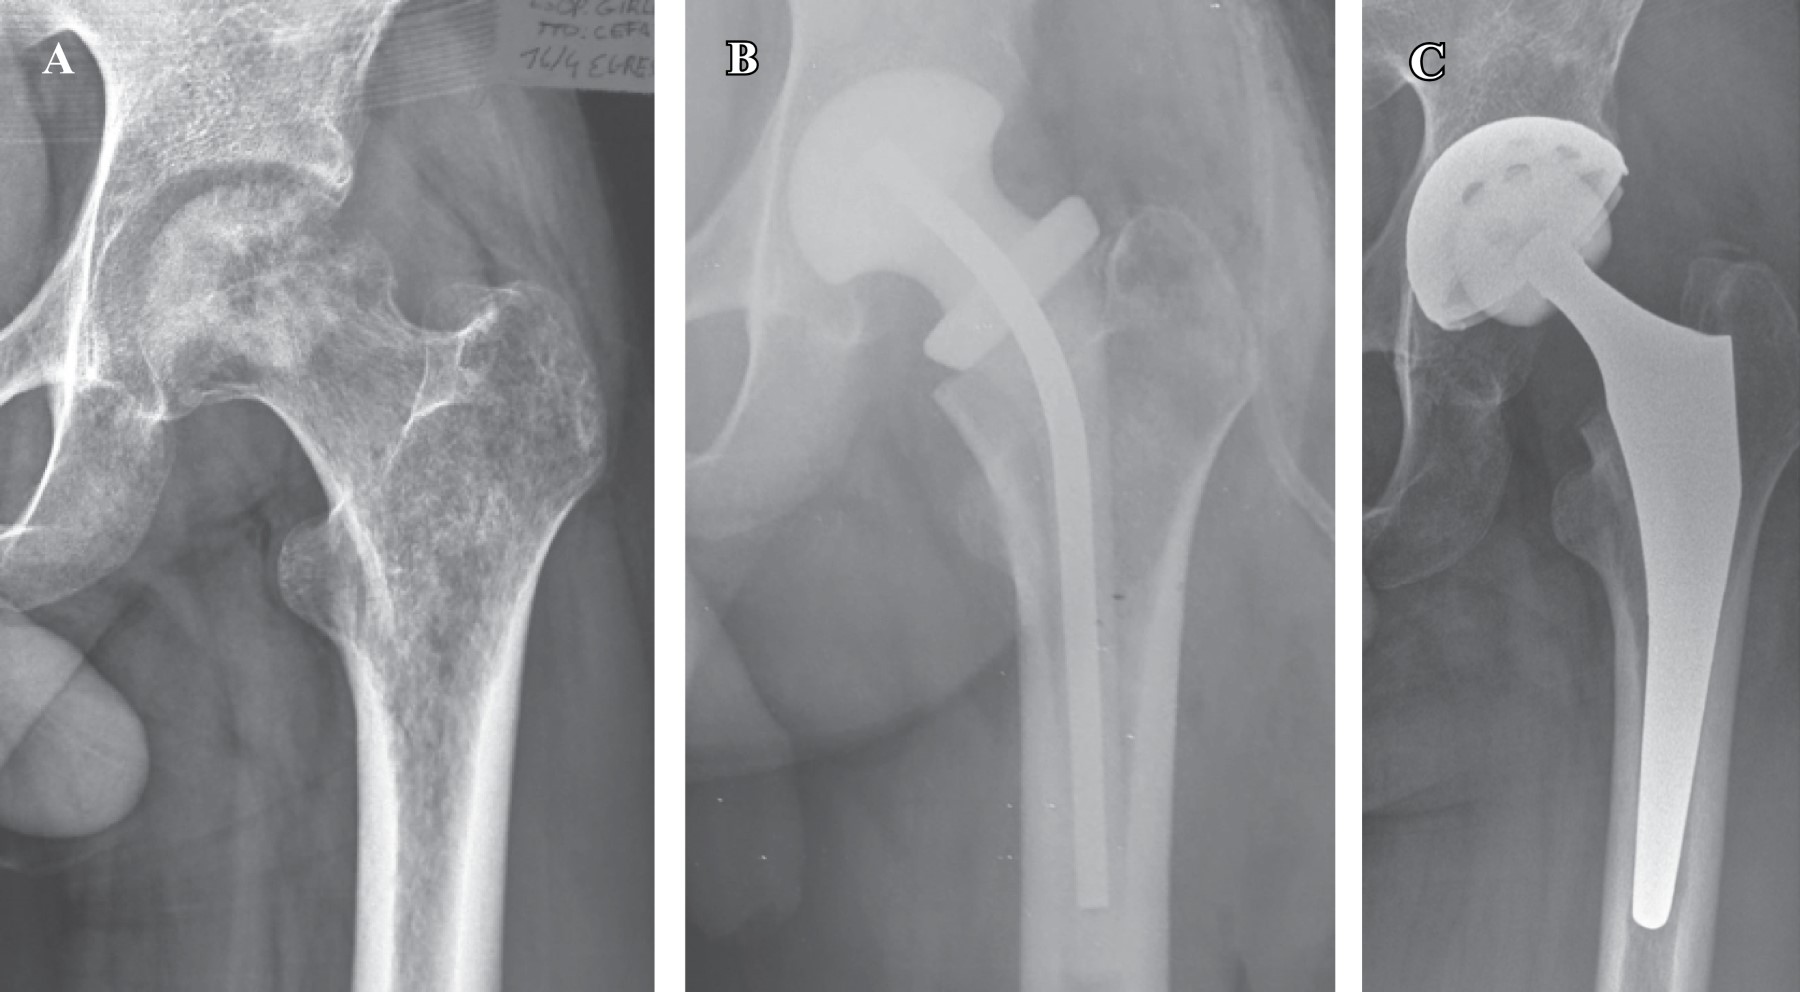

Introducción: La complicación más temida en la artroplastia de cadera después de la artritis séptica (activa o sus secuelas) es el fracaso séptico. El tratamiento en dos etapas, una vez resuelto el proceso infeccioso, es el tratamiento aceptado para la etapa aguda. El objetivo de este trabajo es establecer una pauta terapéutica para la artritis séptica en las caderas nativas, proponiendo un tratamiento en dos etapas para agudos, y un tratamiento de una etapa para las secuelas. Material y métodos: Realizamos un estudio observacional, descriptivo y retrospectivo. Analizamos a todos los pacientes que se sometieron a un reemplazo primario total de cadera en nuestra institución entre Junio de 1997 y Junio de 2016 con un diagnóstico de artritis séptica de la cadera antes de la cirugía (grupo 1: artritis séptica aguda; grupo 2: secuelas de artritis séptica). Resultados: Grupo 1: ocho caderas, con un diagnóstico agudo de artritis séptica y seguimiento de uno a seis años. Se cumplió con el tratamiento antibiótico entre la colocación del espaciador y el reemplazo protésico definitivo, y, en todos los casos, se verificó la remisión de la infección. Grupo 2: 12 caderas, El tiempo entre la infección tratada y el reemplazo de prótesis varió entre cinco y 46 años. Las cabezas femorales enviadas para cultivo eran en todos los casos negativas. Conclusiones: En los últimos 20 años, hemos obtenido resultados satisfactorios, tanto en el tratamiento de la artritis séptica aguda como en sus secuelas, interpretándolas como patologías del mismo origen pero con un tratamiento diferente. Ambos tratamientos son adecuados, siempre y cuando se respete el protocolo terapéutico establecido para cada uno de los grupos.

Figura 2